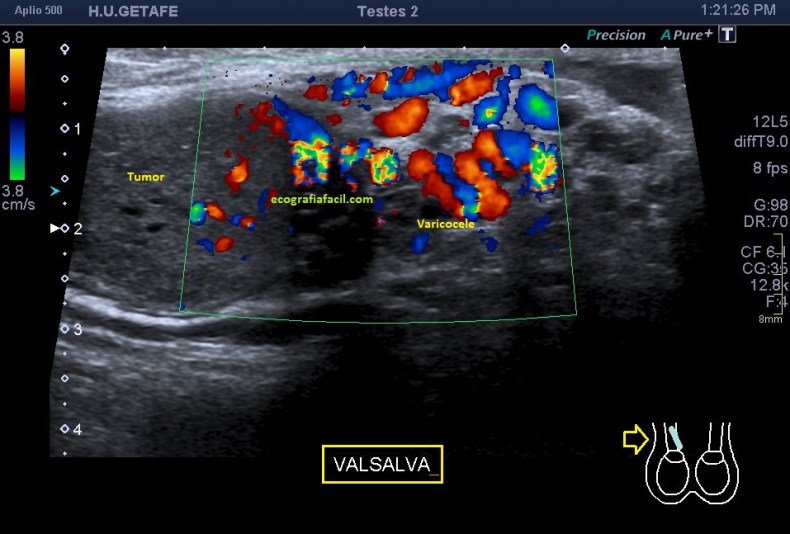

Una vez que tuve controlado el aspecto normal de músculo en la misma localización donde la paciente tenía el bulto, me dirigí a la región del bultoma y estudié la lesión, descrita con anterioridad, siguiendo el protocolo de actuación en caso de neoformaciones, control, medidas, doppler color y power y finalmente comparativa.

El estudio doppler arroja el hallazgo de un vaso importante que está alcanzando y nutriendo la región afectada. Puedes observar como es un vaso de alto flujo y de buen tamaño. No pude demostrar vascularización perimetral de la lesión.